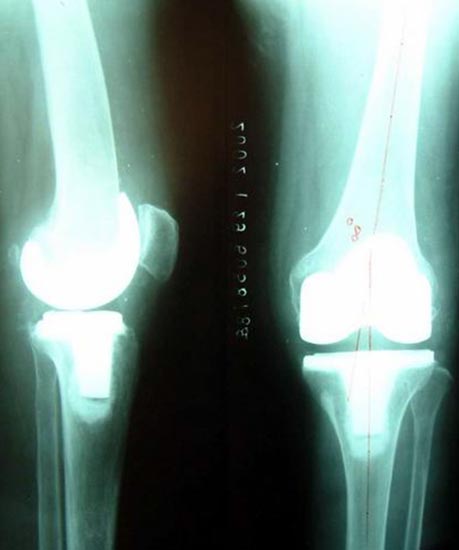

图:切除磨损破坏的关节面,安装平滑的人工关节面,组成新关节

病例一、患者男性,76岁,双膝疼痛10年,屈伸受限,下蹲困难。线片显示双膝骨关节炎改变,关节间隙已经消失。严重膝内翻畸形。

为患者行一期双膝置换术,X线片显示假体位置好,下肢力线恢复。